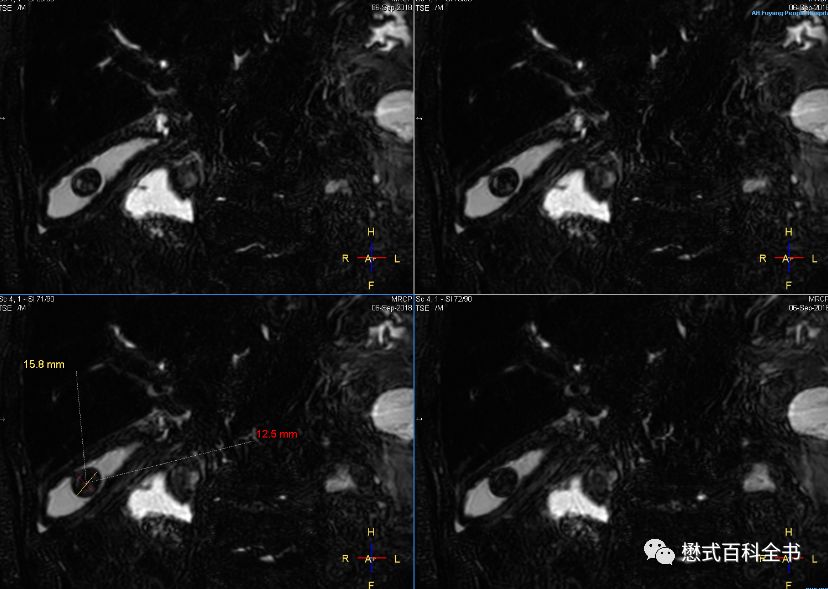

图21:3D MRCP扫描

如图,3D MRCP扫描,容积采集后,然后做MIP(最大信号强度投影重建)。

3D MRCP优点是:信噪比高,可以出薄层图像,而且可以通过图像后处理MIP形成胆管树形结构图,这种图临床医生非常喜欢看,对胆管系统整体结构显示清晰。

但是,3D MRCP也有致命的缺点,如图,如果没有经验的影像医生或者临床医生只看重建的MIP图,而不看原始的薄层图像,则容易出现假阴性(由于最大信号强度投影的图像后处理算法关系,有可能把本来的充盈缺损,显示结石的给遮掩了)。本来有结石的,结果做了MIP后,无法显示充盈缺损了。另外,3D MRCP序列扫描时间也长。

图23:3D MRCP,原始的薄层图像(原始图是非常重要的)

3D MRCP扫描完,一般会进行一些图像后处理,比如MIP,当然也有医院为了图像美观进行裁剪,把多余不要的部分修剪掉。当然,直接MIP生成图像也是可以的。临床医生比较喜欢看重建的MIP图,因为它的胆管树形结构显示清楚。但是,作为放射科医生,一定要注意,在诊断的时候,必须看原始的薄层图。